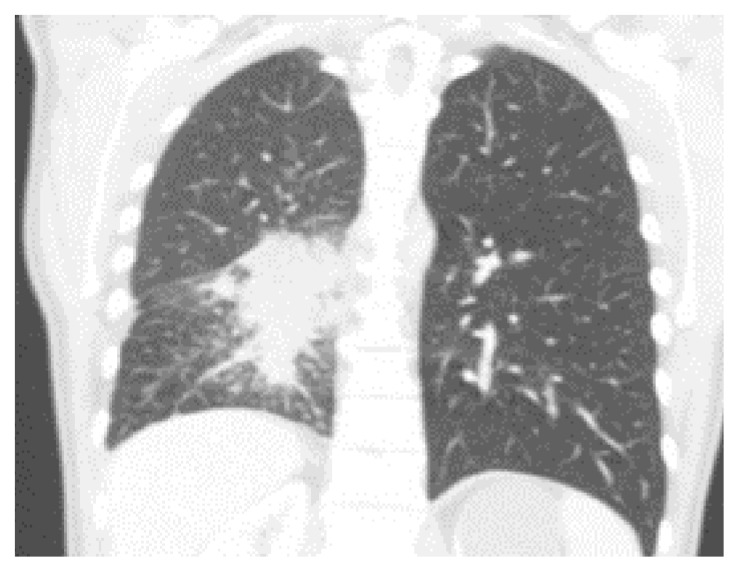

约3%至5%的间变性淋巴瘤激酶(ALK)基因发生致癌重排的个体发展为非小细胞肺癌(NSCLC)。Brigatinib是一种有效的下一代ALK酪氨酸激酶抑制剂(TKI),已显示出显着的全身和颅内反应,以及改善的无进展生存期,具有可接受的安全性。根据欧洲肿瘤医学学会指南,ALK易位和性能状态为0-3的患者可以接受TKI(布加替尼、阿勒替尼或氯拉替尼)一线治疗。据我们所知,这是第一例布加替尼增加剂量后肺部出现囊性或大泡性变化的报道。在这里,我们描述了一个37岁的男性,从不吸烟,在接受布加替尼治疗肺内转移的非小细胞肺癌时,肺实质出现渐进性弥漫性囊性改变。临床医生应该对这种潜在的非典型肺不良反应保持警惕,包括肺实质囊性或大泡性转化的可能性。

Approximately 3% to 5% of individuals with oncogenic rearrangements in the anaplastic lymphoma kinase (ALK) gene develop non-small cell lung cancer (NSCLC). Brigatinib, a potent next-generation ALK tyrosine kinase inhibitor (TKI), has demonstrated significant systemic and intracranial responses, as well as improved progression-free survival, with an acceptable safety profile. According to European Society for Medical Oncology guidelines patients with ALK translocation and performance status 0-3 can be offered 1st line treatment with TKI (brigatinib, alectinib, or lorlatinib). To our knowledge, this is the first reported case of cystic or bullous changes in the lungs following incremental dosing of brigatinib. Here, we describe a 37-year-old male, a never-smoker, who developed progressively diffuse cystic changes in the lung parenchyma while receiving brigatinib treatment for NSCLC with intrapulmonary metastases. Clinicians should remain vigilant for this potential atypical pulmonary adverse effect, including the possibility of cystic or bullous transformations in the lung parenchyma.